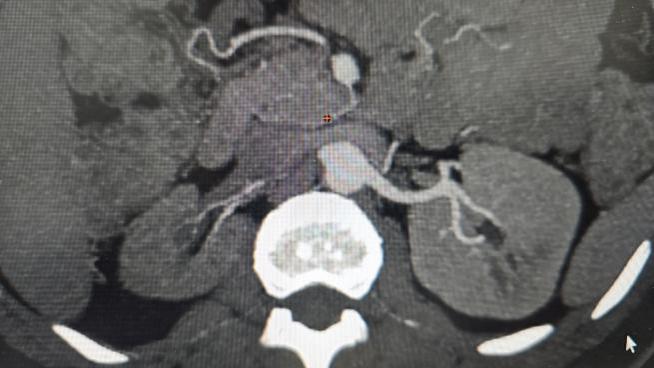

图A 图B

(图A右肾动脉开通前造影,肾动脉起始段闭塞致右肾未显影)(图B右肾动脉开通后造影,可见右肾明确显影)